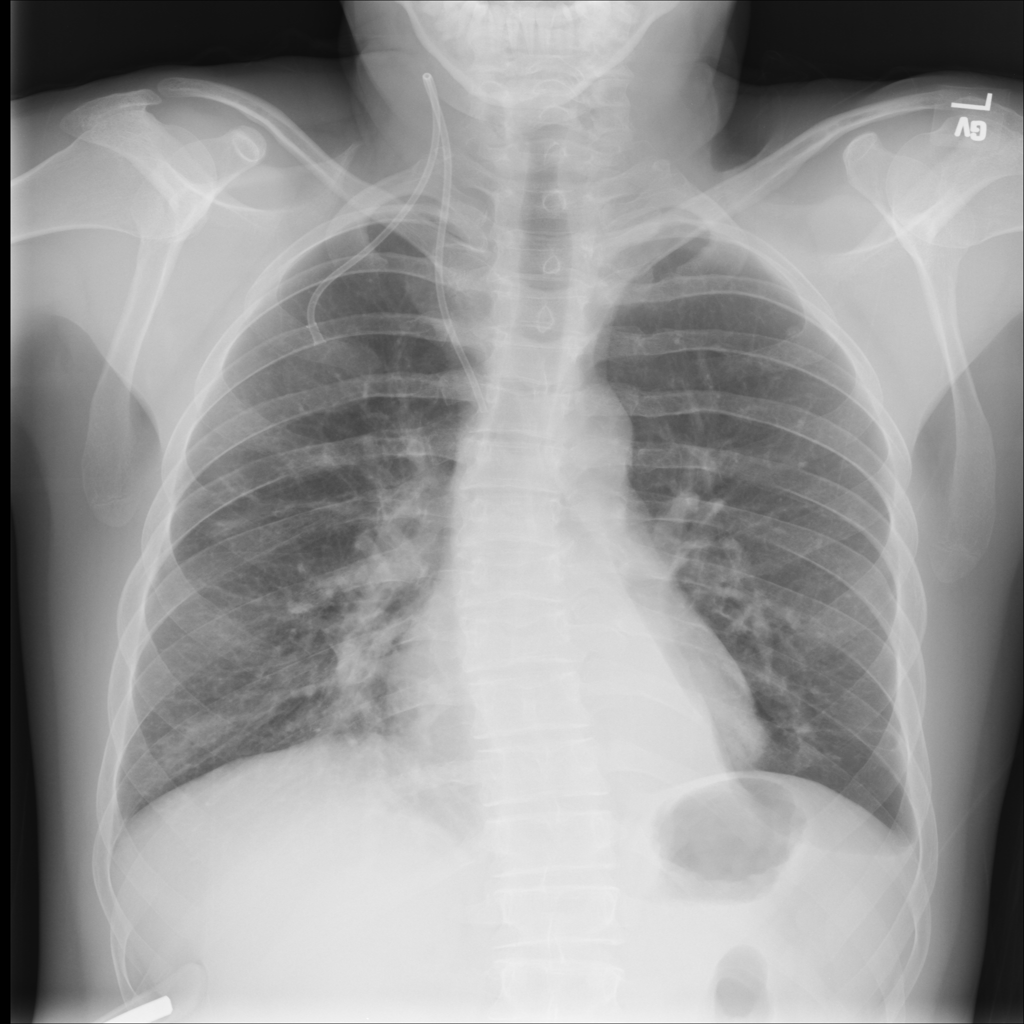

PAT-DB80 · IMG-000Atelectasis

PAT-DB80 · IMG-000

PA